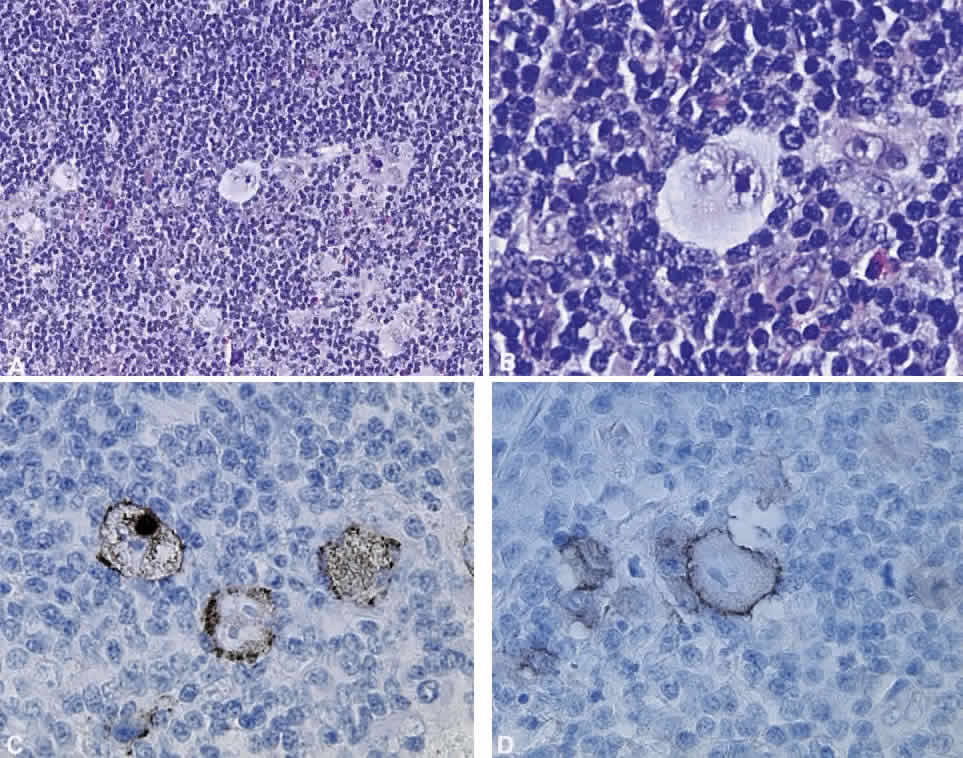

Numerous attempts have been made to classify lymphoid processes for clinical management and prediction of prognosis. Early classifications included only disease localized to the lymph node, which made classification of extranodal disease difficult and inaccurate. The Rappaport classification, first developed in 1956 and then modified in 1978, attempted to categorize lymphomas in two ways, first, using cytologic characteristics identified by conventional stains, and second, distinguishing between the follicular and diffuse growth pattern histologically38,39 (Table 3). The distinction of nodular, or follicular, and diffuse growth was considered useful because of the generally indolent nature of follicular growth, in which the tumor cell aggregates resemble germinal centers and disrupt the normal architecture of the node, compared with the appearance of diffuse growth, in which the lymph node is completely obliterated by a dense monotonous sheet of lymphocytes. In subsequent years, however, it was found that the descriptive growth pattern and cytogenetic characteristics of the Rappaport system did not predict prognosis reliably and were biologically inaccurate. The complexity of correlating degrees of differentiation, mitotic activity, and cytologic characteristics to prognosis have made lymphomas difficult to classify and have led to subsequent systems. The second system, proposed by Lukes-Collins in 1974, classifies lymphoma histologically according to its normal counterpart B-cell, T-cell, or null cell origin40,41 (see Table 3). Histologically, cells may appear small cleaved, large cleaved, small noncleaved, or large noncleaved, depending on the stage of B-cell arrest during normal transformation to immunoblast. Ninety percent of lymphomas are of B-cell origin, and the null cell also usually is of B-cell origin, although 10% may originate from T cells or histiocytes.42,43 Burkitt's lymphoma, the only lymphoma common in children, is a B-cell variant with a background of reactive histiocytes. As a result of histologic classification by Lukes-Collins, 76% of histiocytic lymphomas according to the Rappaport system were found to be not of histiocytic origin but of lymphocytic origin.40,44 The third system, the Working Formulation devised by the National Cancer Institute in 1982, attempted to predict prognosis by grouping lymphoma according to natural history, response to therapy, and overall survival.45 Three broad categories were established in terms of 5-year survival rates, the low-grade with a 50% to 70% survival rate, intermediate with 35% to 45%, and high grade with 23% to 32% (see Table 3). Orbital reactive hyperplasia, a relatively low-grade lesion, can be associated with systemic disease, whereas malignant or high-grade orbital lymphomas may be isolated findings. The Ann Arbor Staging Classification for Hodgkin's and non-Hodgkin's lymphomas was developed to stage disease based on systemic areas of involvement as a means of establishing a baseline for treating disease and following clinical progression46 (Table 4). Histologic classification, however, has been recognized as more useful than localization in the clinical management of nonHodgkin's lymphoma.47

While the Lukes-Collins and Working Formulation classifications were in wide use in the United States, the European literature made references to the Kiel and updated Kiel classifications, which led to disparities in classifying lymphoma. Another classification proposed by Jakobiec and coworkers was the most comprehensive classification available for orbital disease but failed to integrate systemic lymphoma, which is known to be associated in approximately half of cases.1 The most recent classification has made the system universal, comprehensive, and useful to interdisciplinary teams that characteristically manage patients with lymphoma. The International Lymphoma Study Group in 1994 developed the Revised European-American Lymphoma (REAL) classification (Table 5), which classifies lymphoid disease by the cell of origin into B-cell, T-cell, and natural killer cell lymphomas, leukemias, myeloma, and variants of Hodgkin's disease26 (Fig. 4). The identification of the putative benign progenitor cells has been inferred through the use of cell marker studies. The results of molecular genetic studies to identify immunoglobulin gene rearrangements and cytogenetic studies to detect chromosomal translocations in monoclonal proliferations have also been incorporated. A significant contribution of the REAL classification has been to incorporate primary extranodal lymphomas as recognizable and classifiable entities. As a result, new variants in this list include lymphoplasmacytic lymphoma, mantle cell lymphoma, marginal zone B-cell lymphoma, particularly mucosal-associated lymphoid tissue (MALT) lymphoma, subclasses of large cell lymphoma, and the natural killer cell lymphomas. Comparisons of the REAL classification to the Working Formulation and the Kiel classification are shown in Tables 6 and 7, respectively.48 The first series of 112 orbital lymphomas using the REAL classification reported the accuracy and utility of the system in classifying orbital lesions and predicting prognosis in combination with currently available immunophenotyping and immunocytogenetic studies.49 The REAL classification does not classify disease based on the degree of differentiation or clinical prognosis. However, a proposed prognostic scheme has been developed in accordance with the REAL classification28 (Table 8). In this text, tumor nomenclature adheres as strictly as possible to the REAL classification.